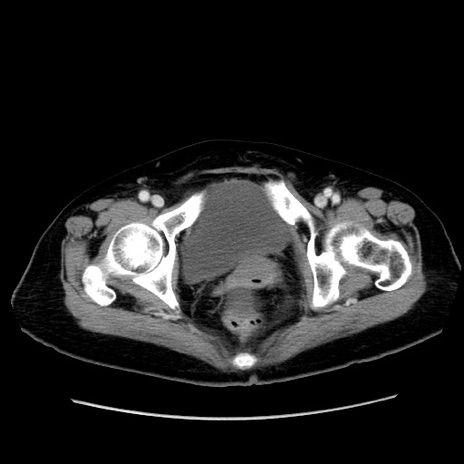

症例19(横断像)

【症例】80歳代女性

【主訴】下腹部痛

【現病歴】約8時間前より下腹部痛の出現あり、救急外来受診。

【既往歴】両側付属器切除

【身体所見】意識清明、下腹部正中に手術痕あり、その部位に一致して圧痛と反跳痛あり。腸蠕動音は亢進。

【データ】WBC 9300、CRP 0.15